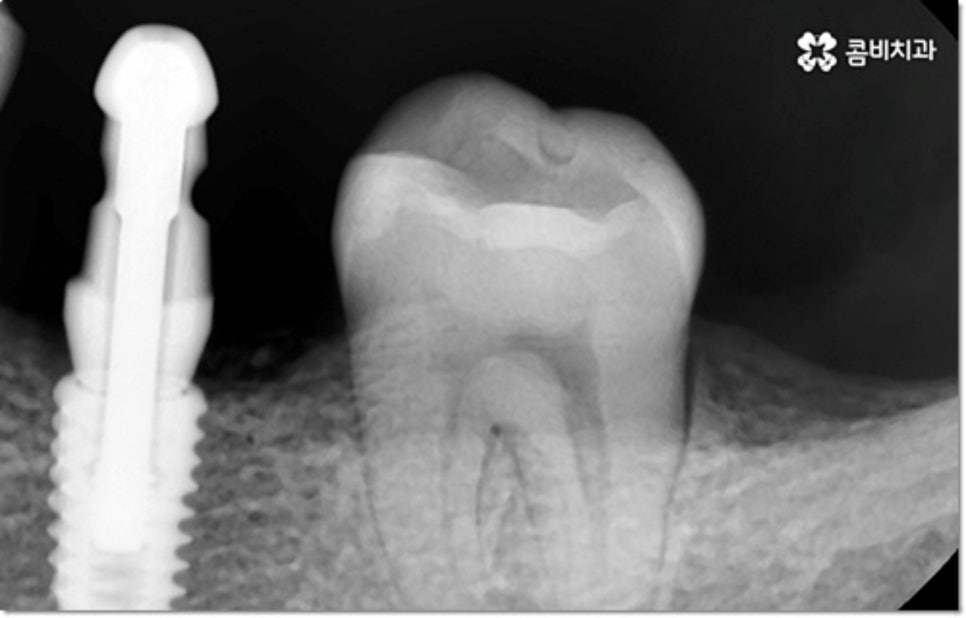

사진에서 볼 수 있는 사례는 아랫니가 크게 부러져서 빠졌을 때 아랫니임플란트 시술을 통해 수복을 해 준 거예요. 이때 빠른 일상 복귀를 원하는 만큼 기간이 얼마나 오래 걸리는가 하는 것은 임플란트 시술을 받으시는 분들의 가장 주된 관심사 중 하나라고 할 수 있는데요.

임플란트 시술 기간은 환자분들의 상황에 따라 달라지는 것이지만 보통 빠르면 36개월, 뼈이식이나 상악동 거상술과 같은 선처치가 필요한 경우 또는 회복 기간이 생각보다 오래 걸리는 경우에는 8개월1년 넘게 까지도 걸릴 수 있습니다. 혹시 모를 부작용으로 재시술을 받게 되는 경우도 있기 때문에 치과를 선택하실 때 말씀드린 의료진의 숙련도 외에도 여러 가지 사항들을 꼼꼼하게 따져보실 필요가 있어요. 3D CT 와 같은 정밀 장비로 환자분들의 잇몸 상황 또는 교합 등을 세밀하게 살펴보고 그에 맞춰 무리하지 않게 임플란트 식립을 진행하는 치과에서 검진부터 사후관리까지 체계적으로 케어받는 것이 중요한 거예요.